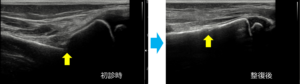

これまでのものより画質が良く、より細かな描出ができるようになりました。

手首の骨折(橈骨遠位端部骨折)

手首の腱鞘炎

足首の靭帯断裂

鎖骨骨折(10日後)

野球肘